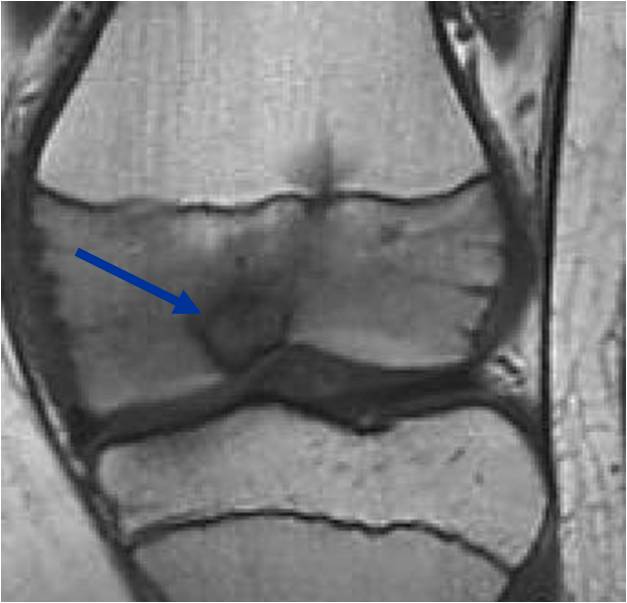

General Information Enchondroma is a benign indolent intramedullary hyaline cartilage neoplasm Accounts for 10% of all benign osseous tumors Limited growth, most lesions are less than 5 cm in maximal dimension Bones grow from a cartilaginous growth plate that...